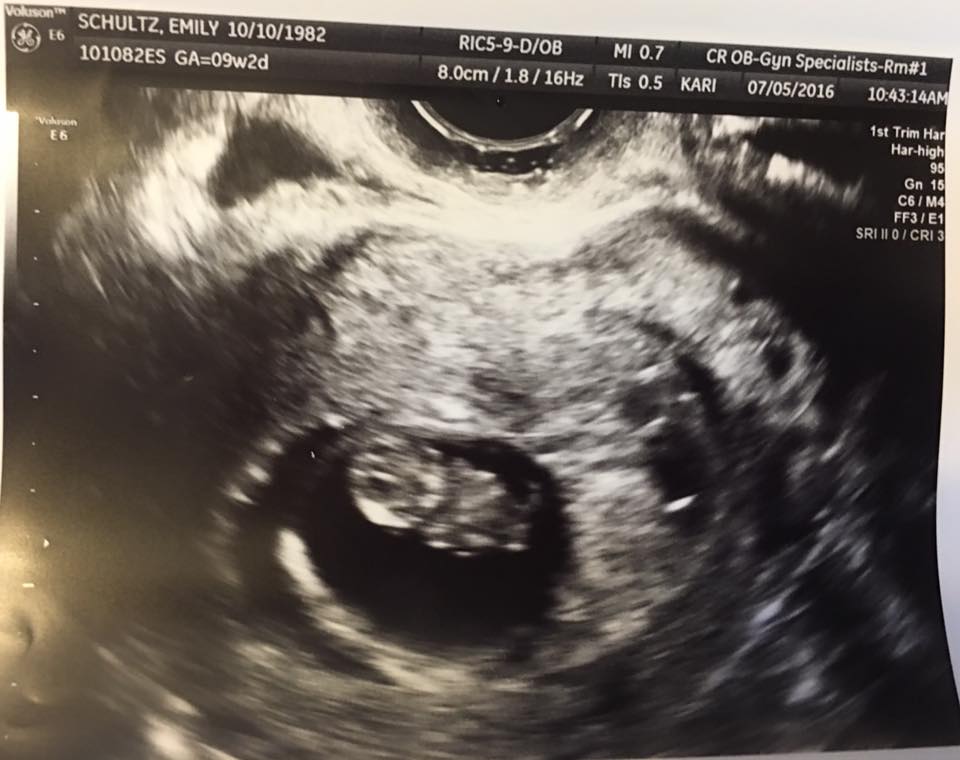

Anyone good at Ramzi method?? I have had four scans this pregnancy so far due to a SCH at 6, 7, 8, and today at 9+2. Just wondering your thoughts on this method, I know it's early and not 100% ;-)

Attachment 32033Attachment 32034Attachment 32035Attachment 32036